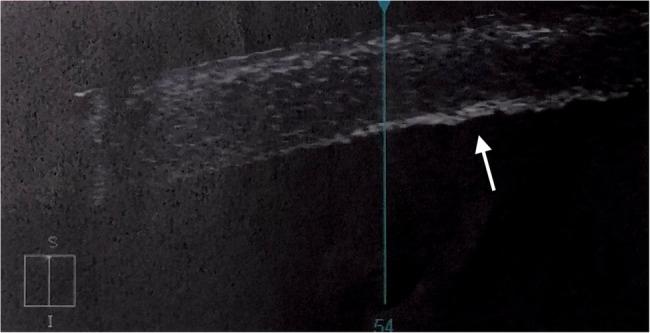

到暴露后第三周,右眼水肿和浅表染色几乎完全消失。双眼未矫正视力提高到0.3,对眼镜矫正有反应。之前的治疗方案又继续了一周。然而,在角膜下部的内皮水平上发现了一个1毫米的丝状疤痕(图3)。前节OCT检查证实了这一发现,即内皮细胞高信号强度增厚的焦点区域(图4)。接触后一个月和两个月的电话随访证实,眼部状况稳定,右眼内皮丝状瘢痕持续存在。

图4 OCT扫描显示内皮丝状瘢痕为高信号强度增厚的焦点区域(白色箭头)(马拉松后3周)